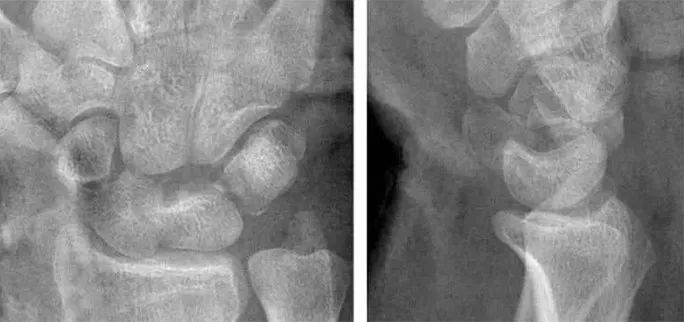

侧位显示月骨向掌侧倾斜

Case 分析

1.月骨-三角骨间隙平行关系缺失致掌骨弧线I and II中断。

2.月骨和舟骨平行,而与其他腕骨不平行。

3.舟骨缩短提示向掌侧倾斜。

4.月骨平行于舟骨,其三角形状提示为掌侧倾斜所致。

5.近排腕骨不是一个整体,因为弧线I中断。

诊断:掌屈不稳伴月骨-三角骨关节脱位